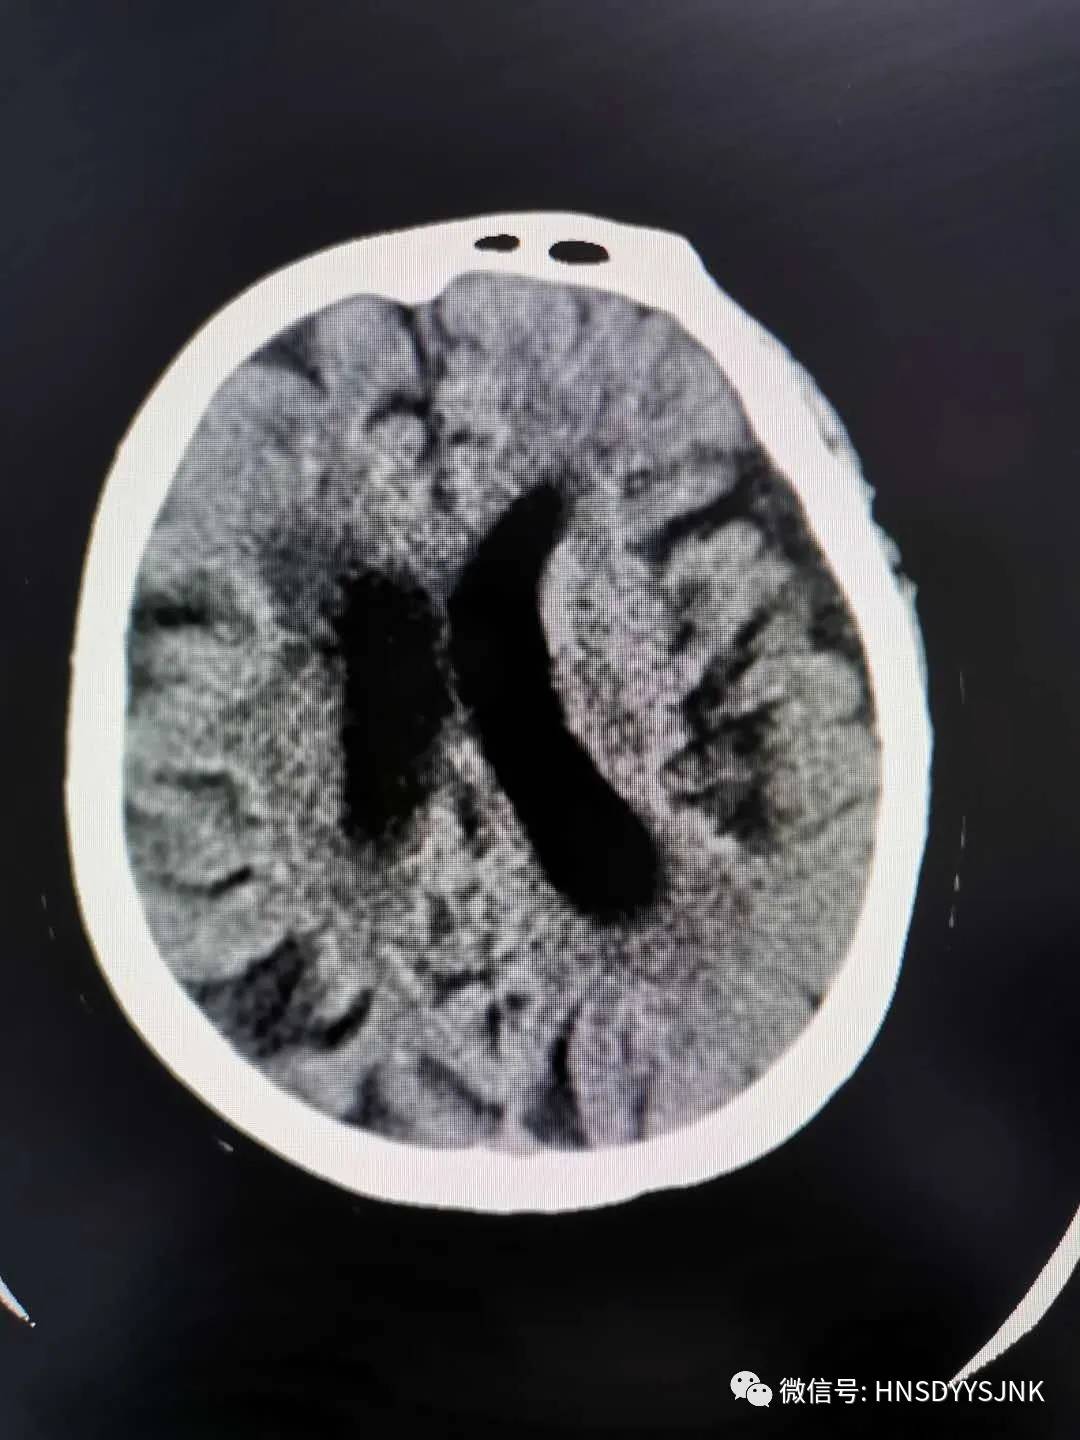

2月28日,急诊科电话通知神经内科,有卒中病人可能需要静脉溶栓。原来是一位72岁的老人,她突发右侧肢体无力,急诊科医生快速评估后,考虑急性脑卒中,立即启动卒中绿色通道。

(溶栓前患者情况)

为了杜绝新冠肺炎的交叉感染,急诊科医师和神经内科医师一起快速核查排,并除新冠病毒感染后,在科室副主任指导下,神经内科医护人员有条不紊的做好静脉溶栓工作。严密紧张地监测患者生命体征、溶栓效果及是否出现并发症,溶栓进行半小时后,患者右侧肢体肌力恢复正常,家属对溶栓效果满意。

(溶栓后患者情况)